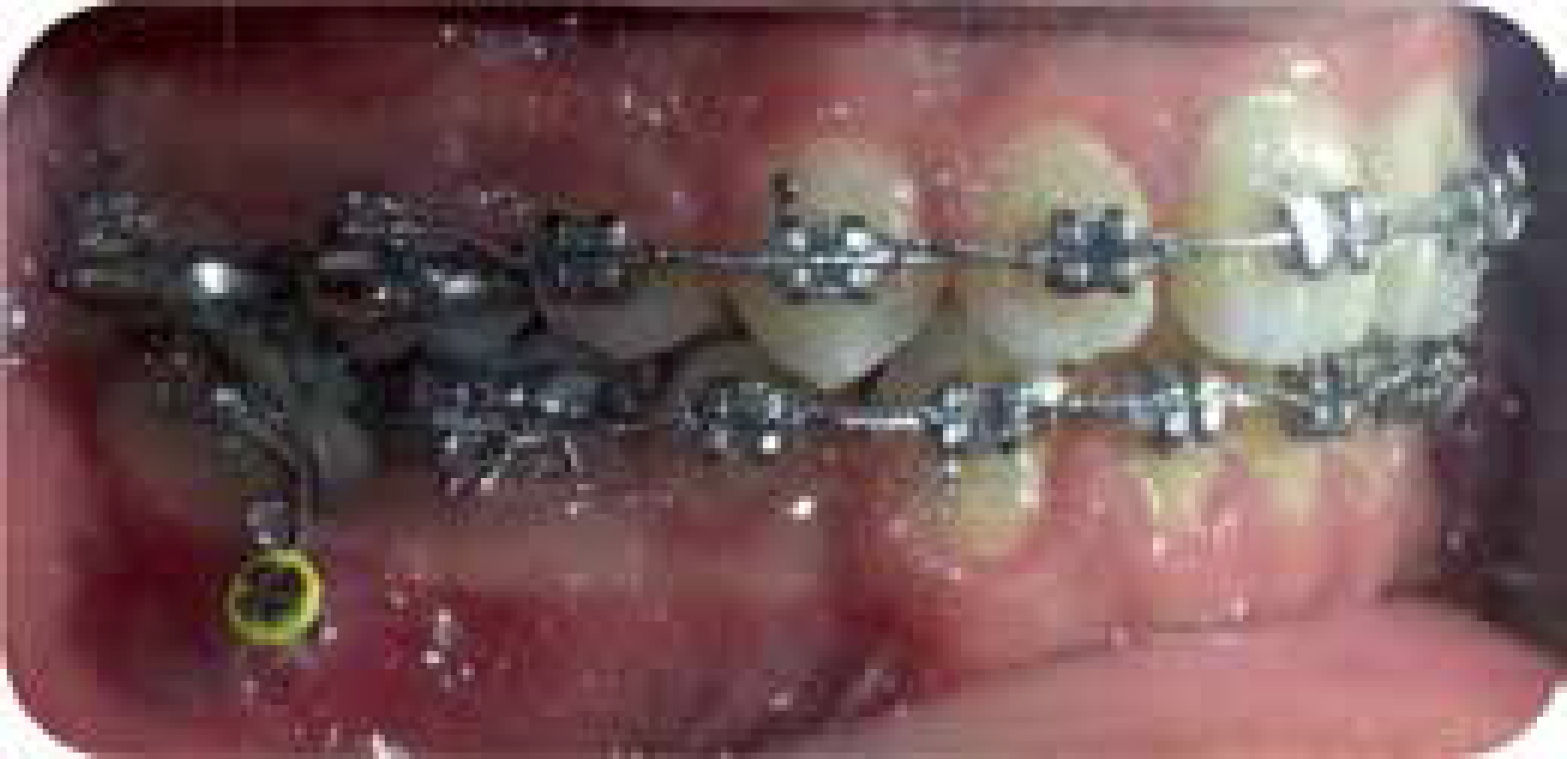

Phase II. 0.019” x 0.025” SS archwires. Activelacebacks. During this phase, an 8 mm-length mini-implant was placed in the buccal area between the roots of the lower right first and second molars (Figure 6). After a month from the placement of the mini-implant a spring was used with a parallelization bend to direct the crown of the dental organ #47 (D.O. distally (Figure 7).